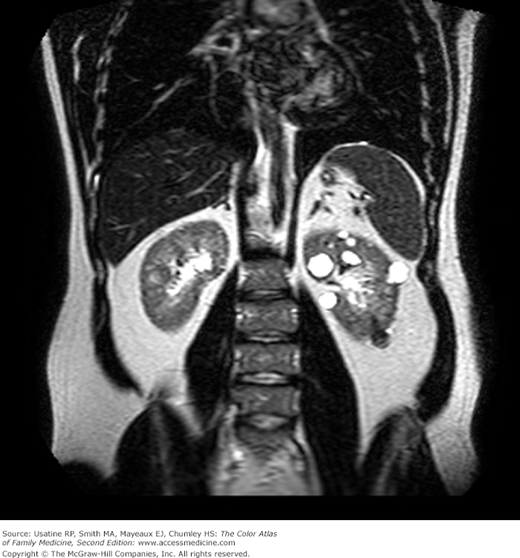

Kidney cancer, abdominal CT scan Stock Image M134/0458 Science Can A Chest Xray Show Kidney Cancer An ultrasound scan can show if there are any signs of cancer in your kidneys. Today, most kidney tumors are found incidentally during imaging studies such as ultrasound, ct scan or mri. Kidney cancer is a growth of cells that starts in the kidneys. While some small tumors are. But more often this can be seen on a ct scan. Can A Chest Xray Show Kidney Cancer.